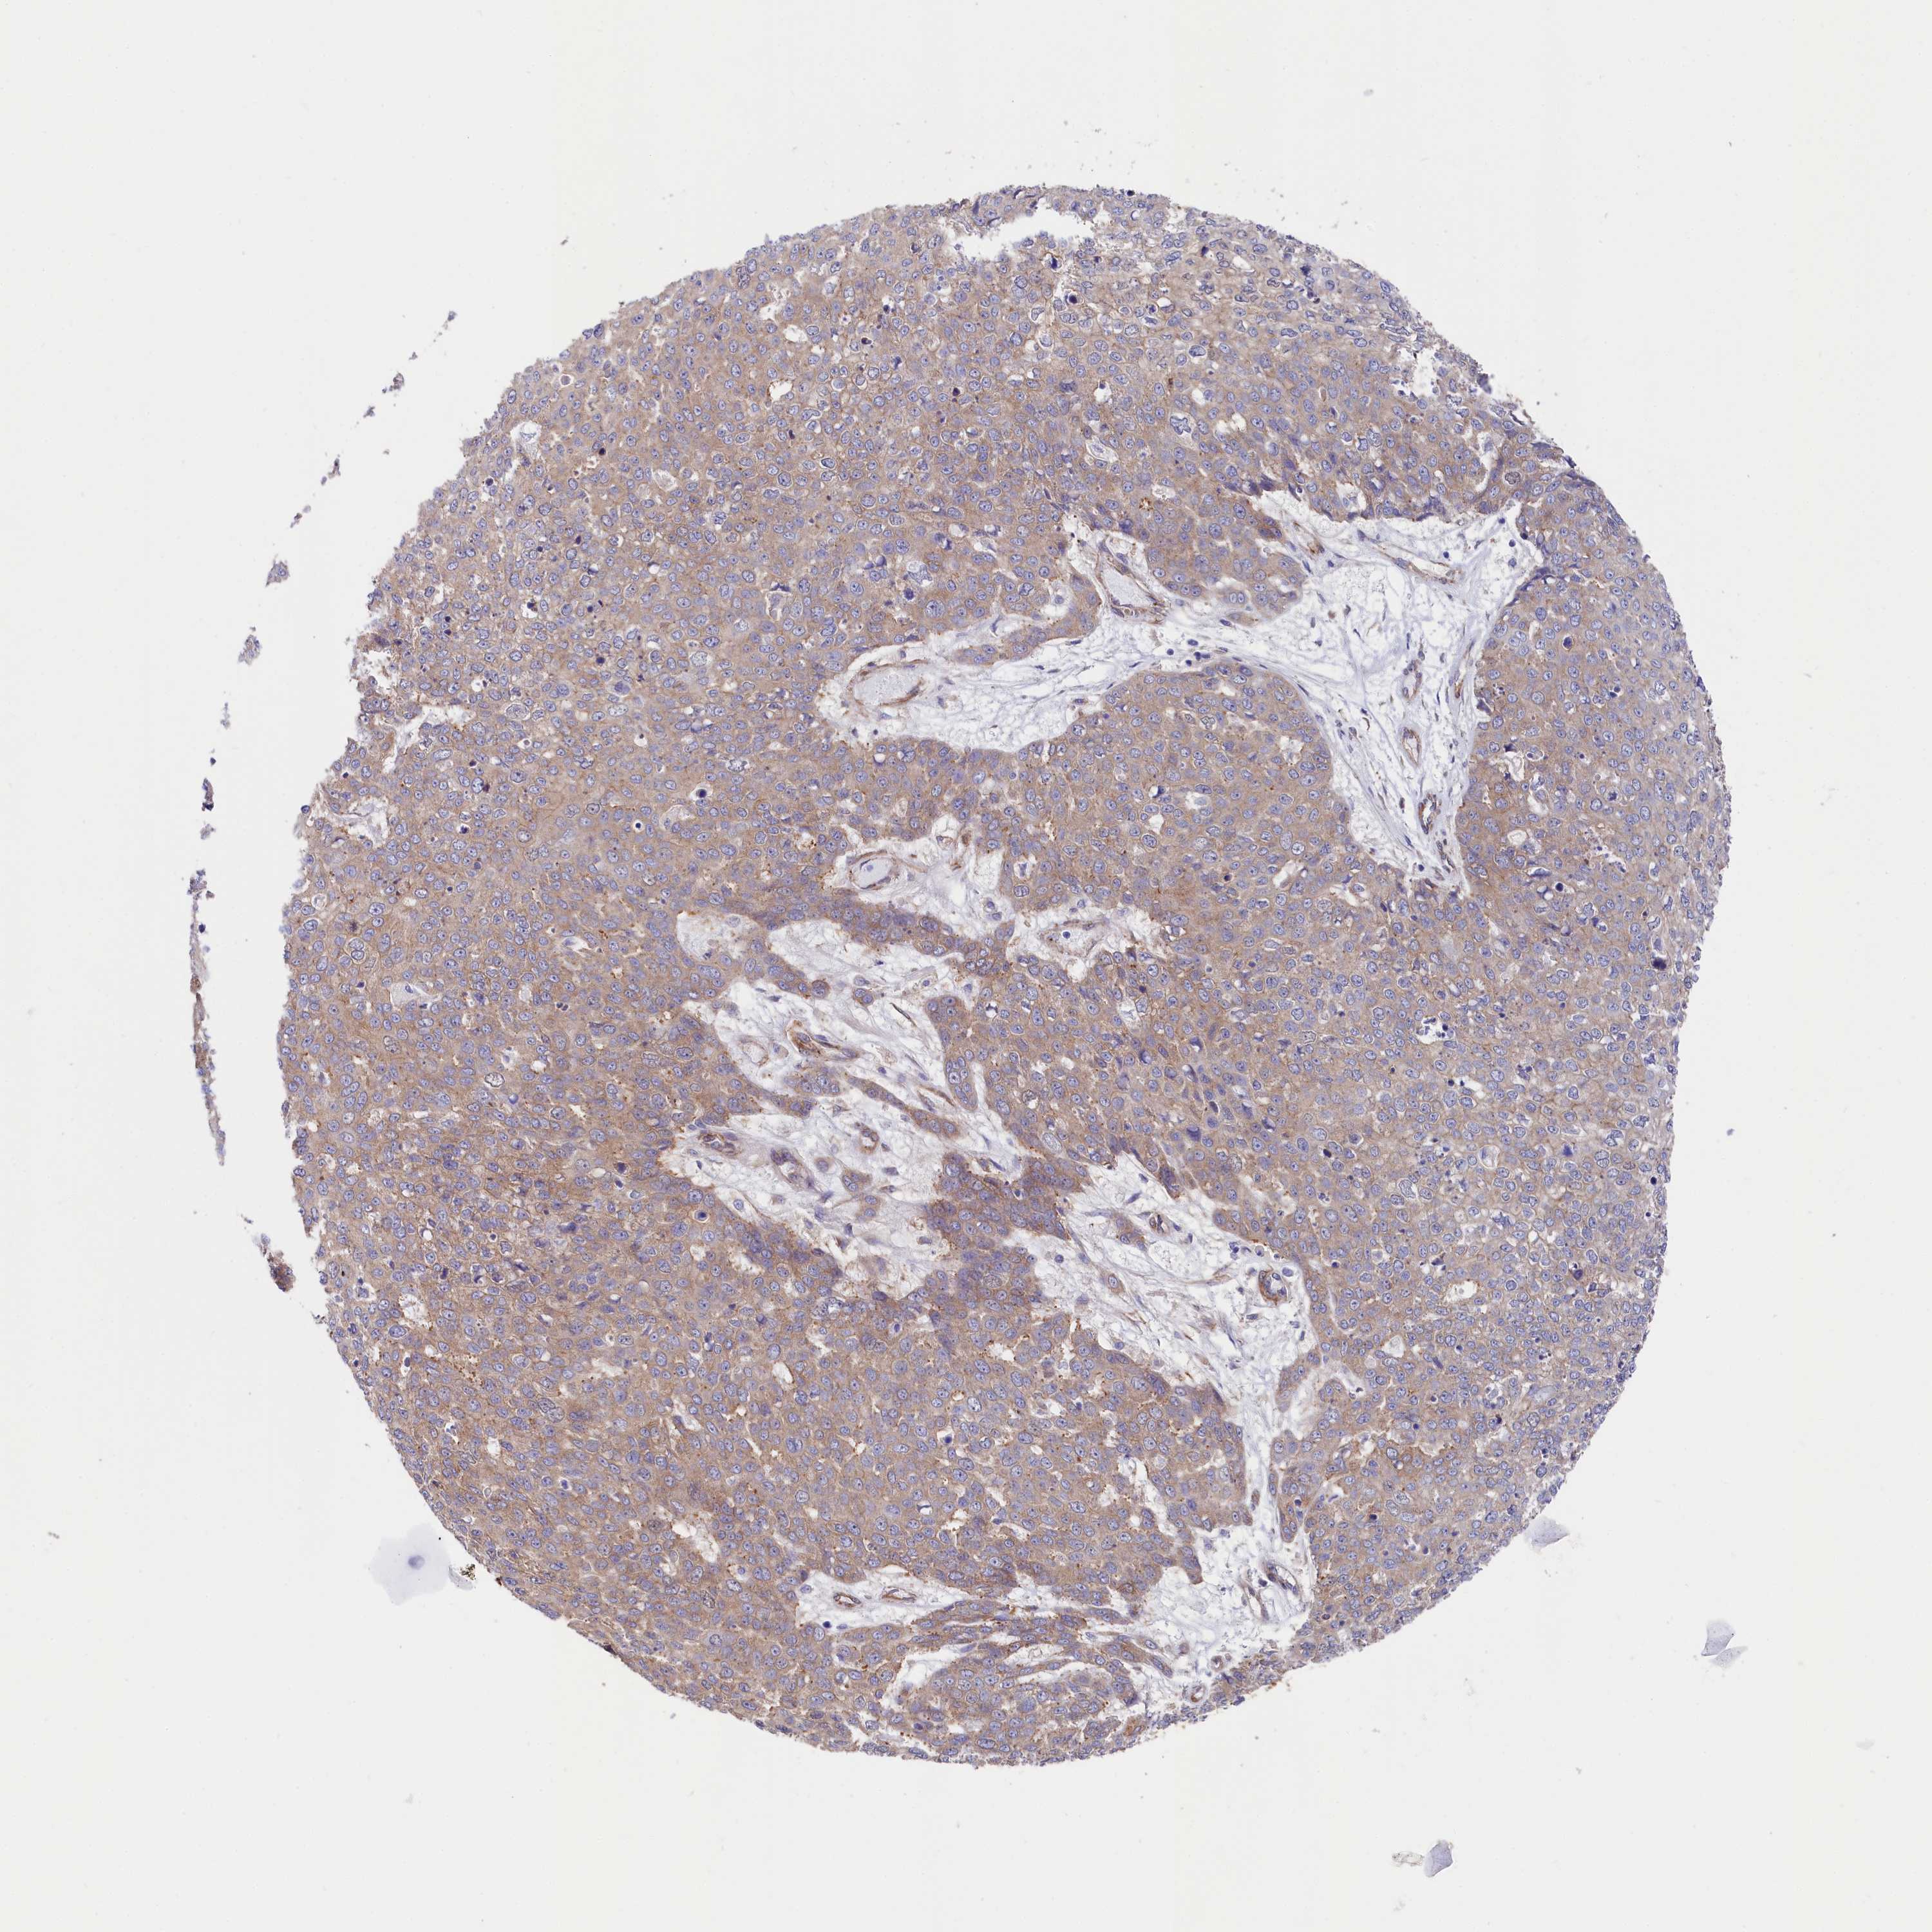

SKIN CANCER - Protein expressioni

A mouse-over function shows sample information and annotation data. Click on an image to view it in a full screen mode. Samples can be filtered based on level of antibody staining by selecting one or several of the following categories: high, medium, low and not detected. The assay and annotation is described here.

Antibody stainingi

Antibody staining in the annotated cell types in the current human tissue is reported as not detected, low, medium, or high, based on conventional immunohistochemistry profiling in selected tissues. This score is based on the combination of the staining intensity and fraction of stained cells.

Each image is clickable and will lead to virtual microscopy that enables deeper exploration of all samples and also displays staining intensity scores, fraction scores and subcellular localization as well as patient and tissue information for each sample.

Antibody HPA037929

Antibody HPA037930

Staining

High

Medium

Low

Not detected

Intensity

Strong

Moderate

Weak

Negative

Quantity

>75%

75%-25%

<25%

None

Location

Nuclear

Cytoplasmic/membranous

Cytoplasmic/membranous,nuclear

Basal cell carcinoma

Squamous cell carcinoma, NOS

Squamous cell carcinoma, metastatic, NOS